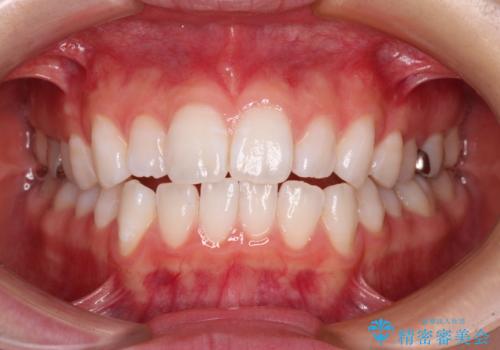

【モニター】口が閉じにくい 膨らんだ口元を抜歯矯正ですっきりと

- 前歯の出っ歯と口元の閉じにくさを気にして来院された患者様です。

口元を積極的に引っ込めるために、上下左右の小臼歯4本を抜歯することとしました。

4本の歯を抜歯したことで、飛び出していた口元が引っ込み、横顔が大きく改善されました。